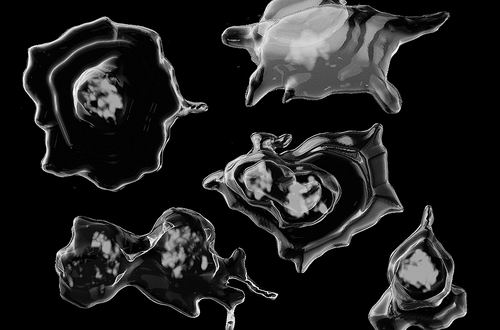

血小板可从血液中捕获DNA。图片来源:LAUREN MURPHY